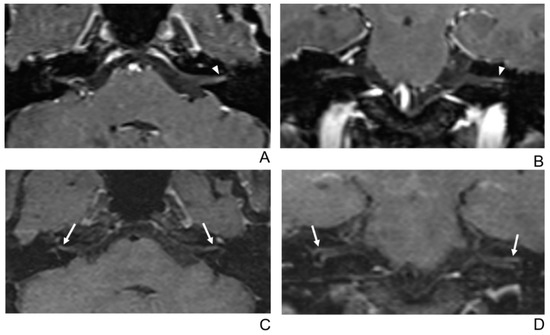

Figure 5.

A 68-year-old female without symptoms of facial palsy (normal control). (A–D) Paired axial and coronal CE-GRE (A,B) and T1 BB-FSE (C,D) images of bilateral facial nerves. The only distal canalicular segment of the left facial nerve demonstrates moderate asymmetric enhancement in the axial (A) and coronal (B) CE-GRE images (arrowheads); thus, each reviewer interpreted it as left facial neuritis (false positive; 1, diagnostic confidence; 2, visual grade for contrast enhancement in the canalicular segment). In contrast, the bilateral facial nerves showed no significantly asymmetric enhancement in the T1 BB-FSE axial (C) and coronal (D) images (arrows); two reviewers evaluated it as normal facial nerves (true negative).